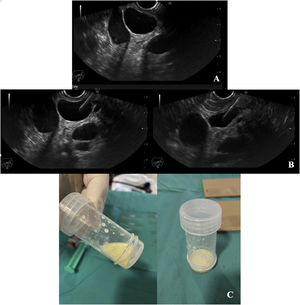

A 44-year-old white male was referred to a Gastroenterology consultation after an abdominal computed tomography (CT) showed a 22mm hypodense nodular image located between the inferior vena cava (IVC) and the second part of the duodenum externally to the splenomesaic confluent, whose density suggested a liquid/cystic nature. The physical examination and laboratory test results were unremarkable. An endoscopic ultrasound (EUS) was requested and showed a 23mm cystic lesion with a well-defined and regular wall located between the IVC and the cephalic portion of the pancreas; the lesion was next to the pancreatic parenchyma, raising the hypothesis of a pancreatic cystic lesion. Fine needle aspiration (FNA) biopsy revealed a milky fluid with a yellowish color that might correspond to lymph, suggesting the possibility of a lymphangioma (Fig. 1). Cytological and biochemical exam of the fluid revealed 18,000 nucleated cells/μL with a lymphocyte predominance and a background of proteinaceous material; an elevated triglyceride value (2953.3mg/dL); amylase (351U/L) and carcinoembryonic antigen (CEA) (8.84ng/mL) within normal limits. All these aspects support the diagnosis of peripancreatic lymphangioma. As the patient was asymptomatic, a conservative approach with imaging surveillance was chosen. The patient will be re-evaluated in six months.